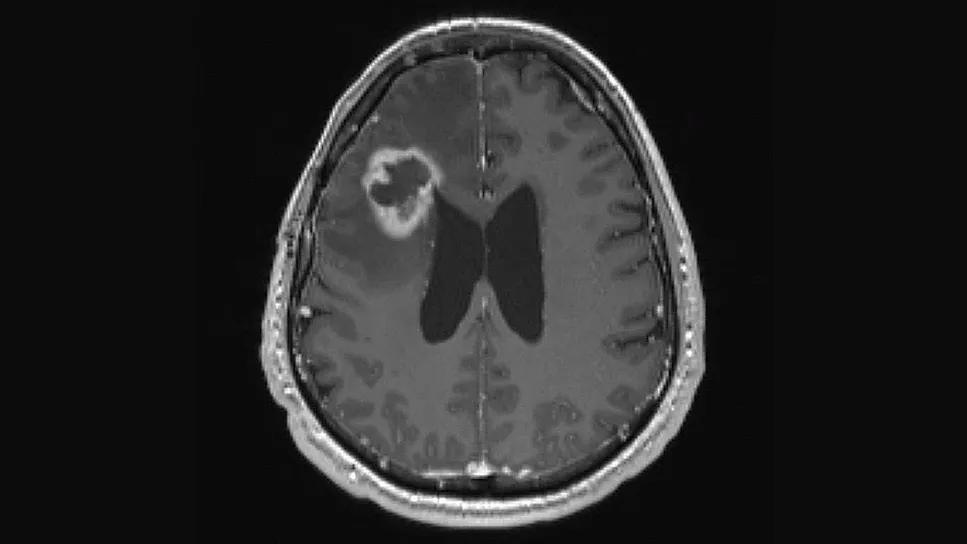

brain scan showing a large white-rimmed lesion in top left portion